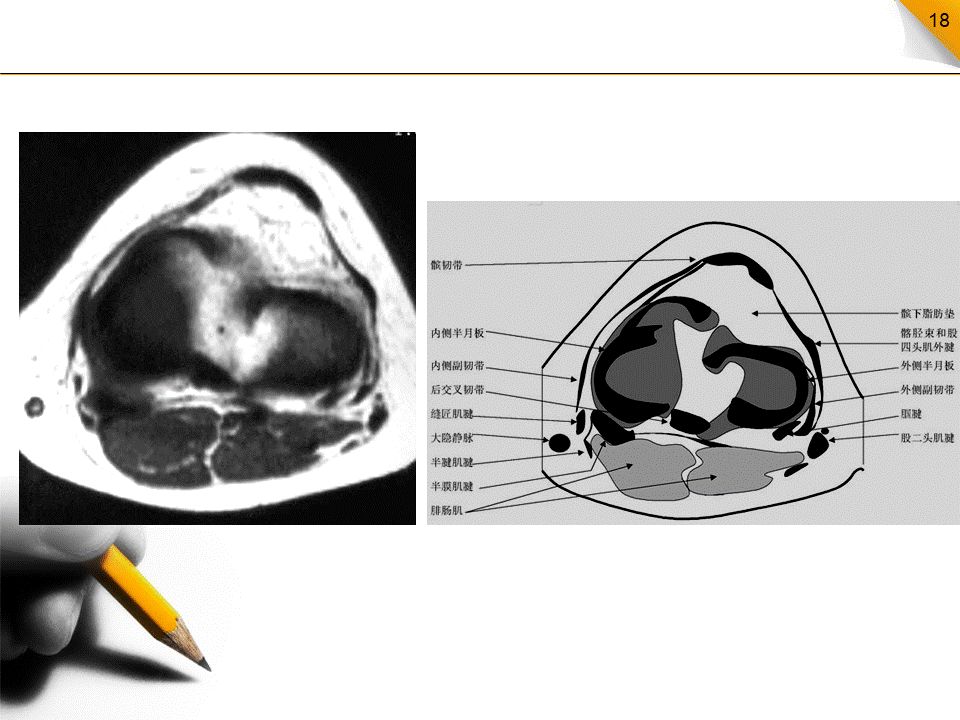

膝关节MR解剖(横断面)

是三维影像首选的方位,也是为了便于MRI与CT比较可准确地展现髌骨内外侧关节面